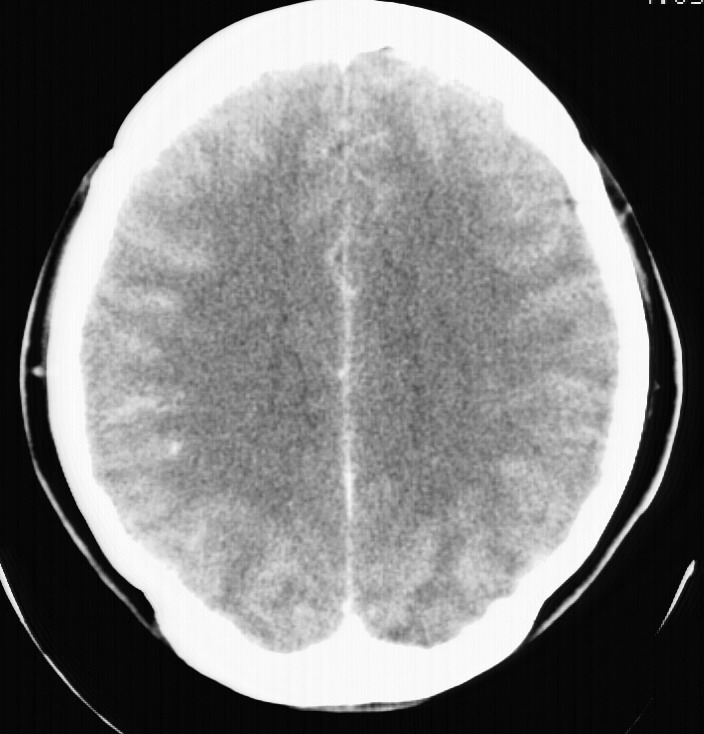

标题: CT5853:右额叶上部占位请会诊

女,34岁,自述头晕胀2年,近期感精神恍惚,无发热,实验室检查阴性。

右顶叶靠近脑表面圆形低密度灶,周围无水肿及占位效应,增强病灶无明显强化,考虑:右顶叶低分级星型细胞瘤。

右额叶上部皮质区见类圆形低密度区,边界不清,无强化,无钙化。

支持大多数战友的意见,1级星形细胞瘤。